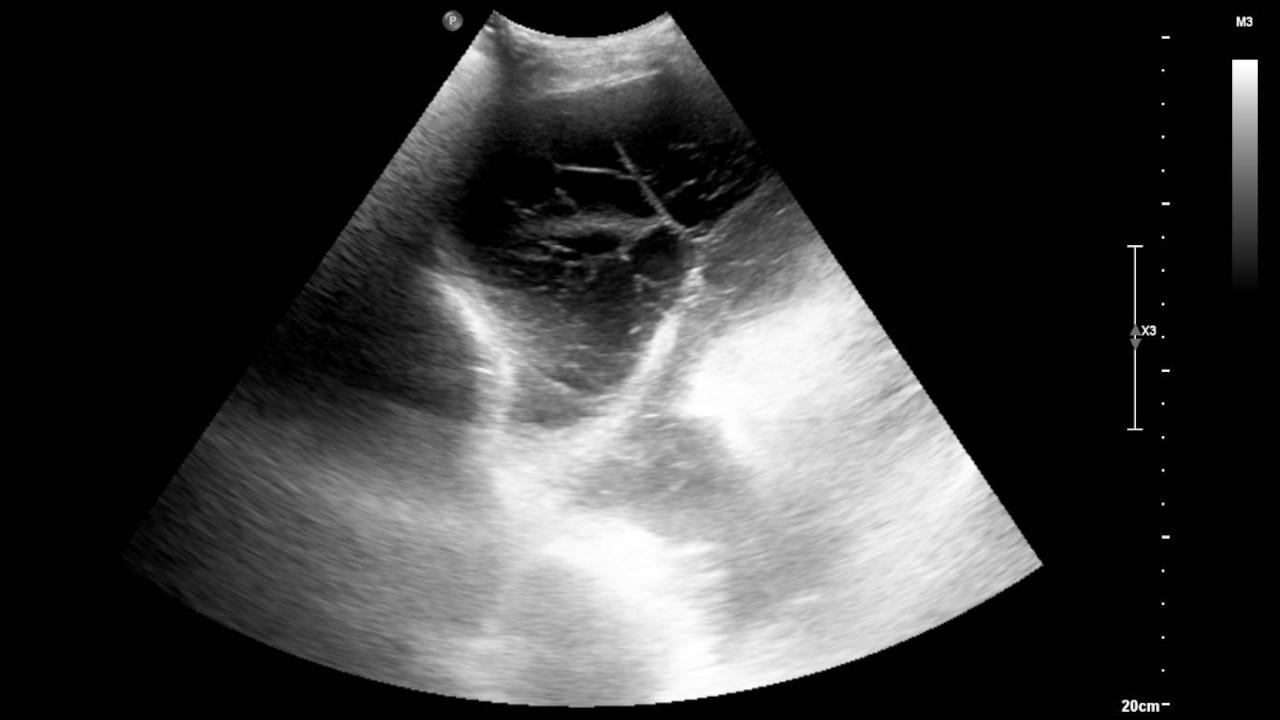

88-year-old male - S Costantino, MT Khan, M Shafiq and K Mustafa